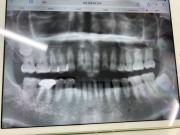

画像1:2024年3月 ジルコニアを外して根幹治療が終わった後に撮影したもの

画像1